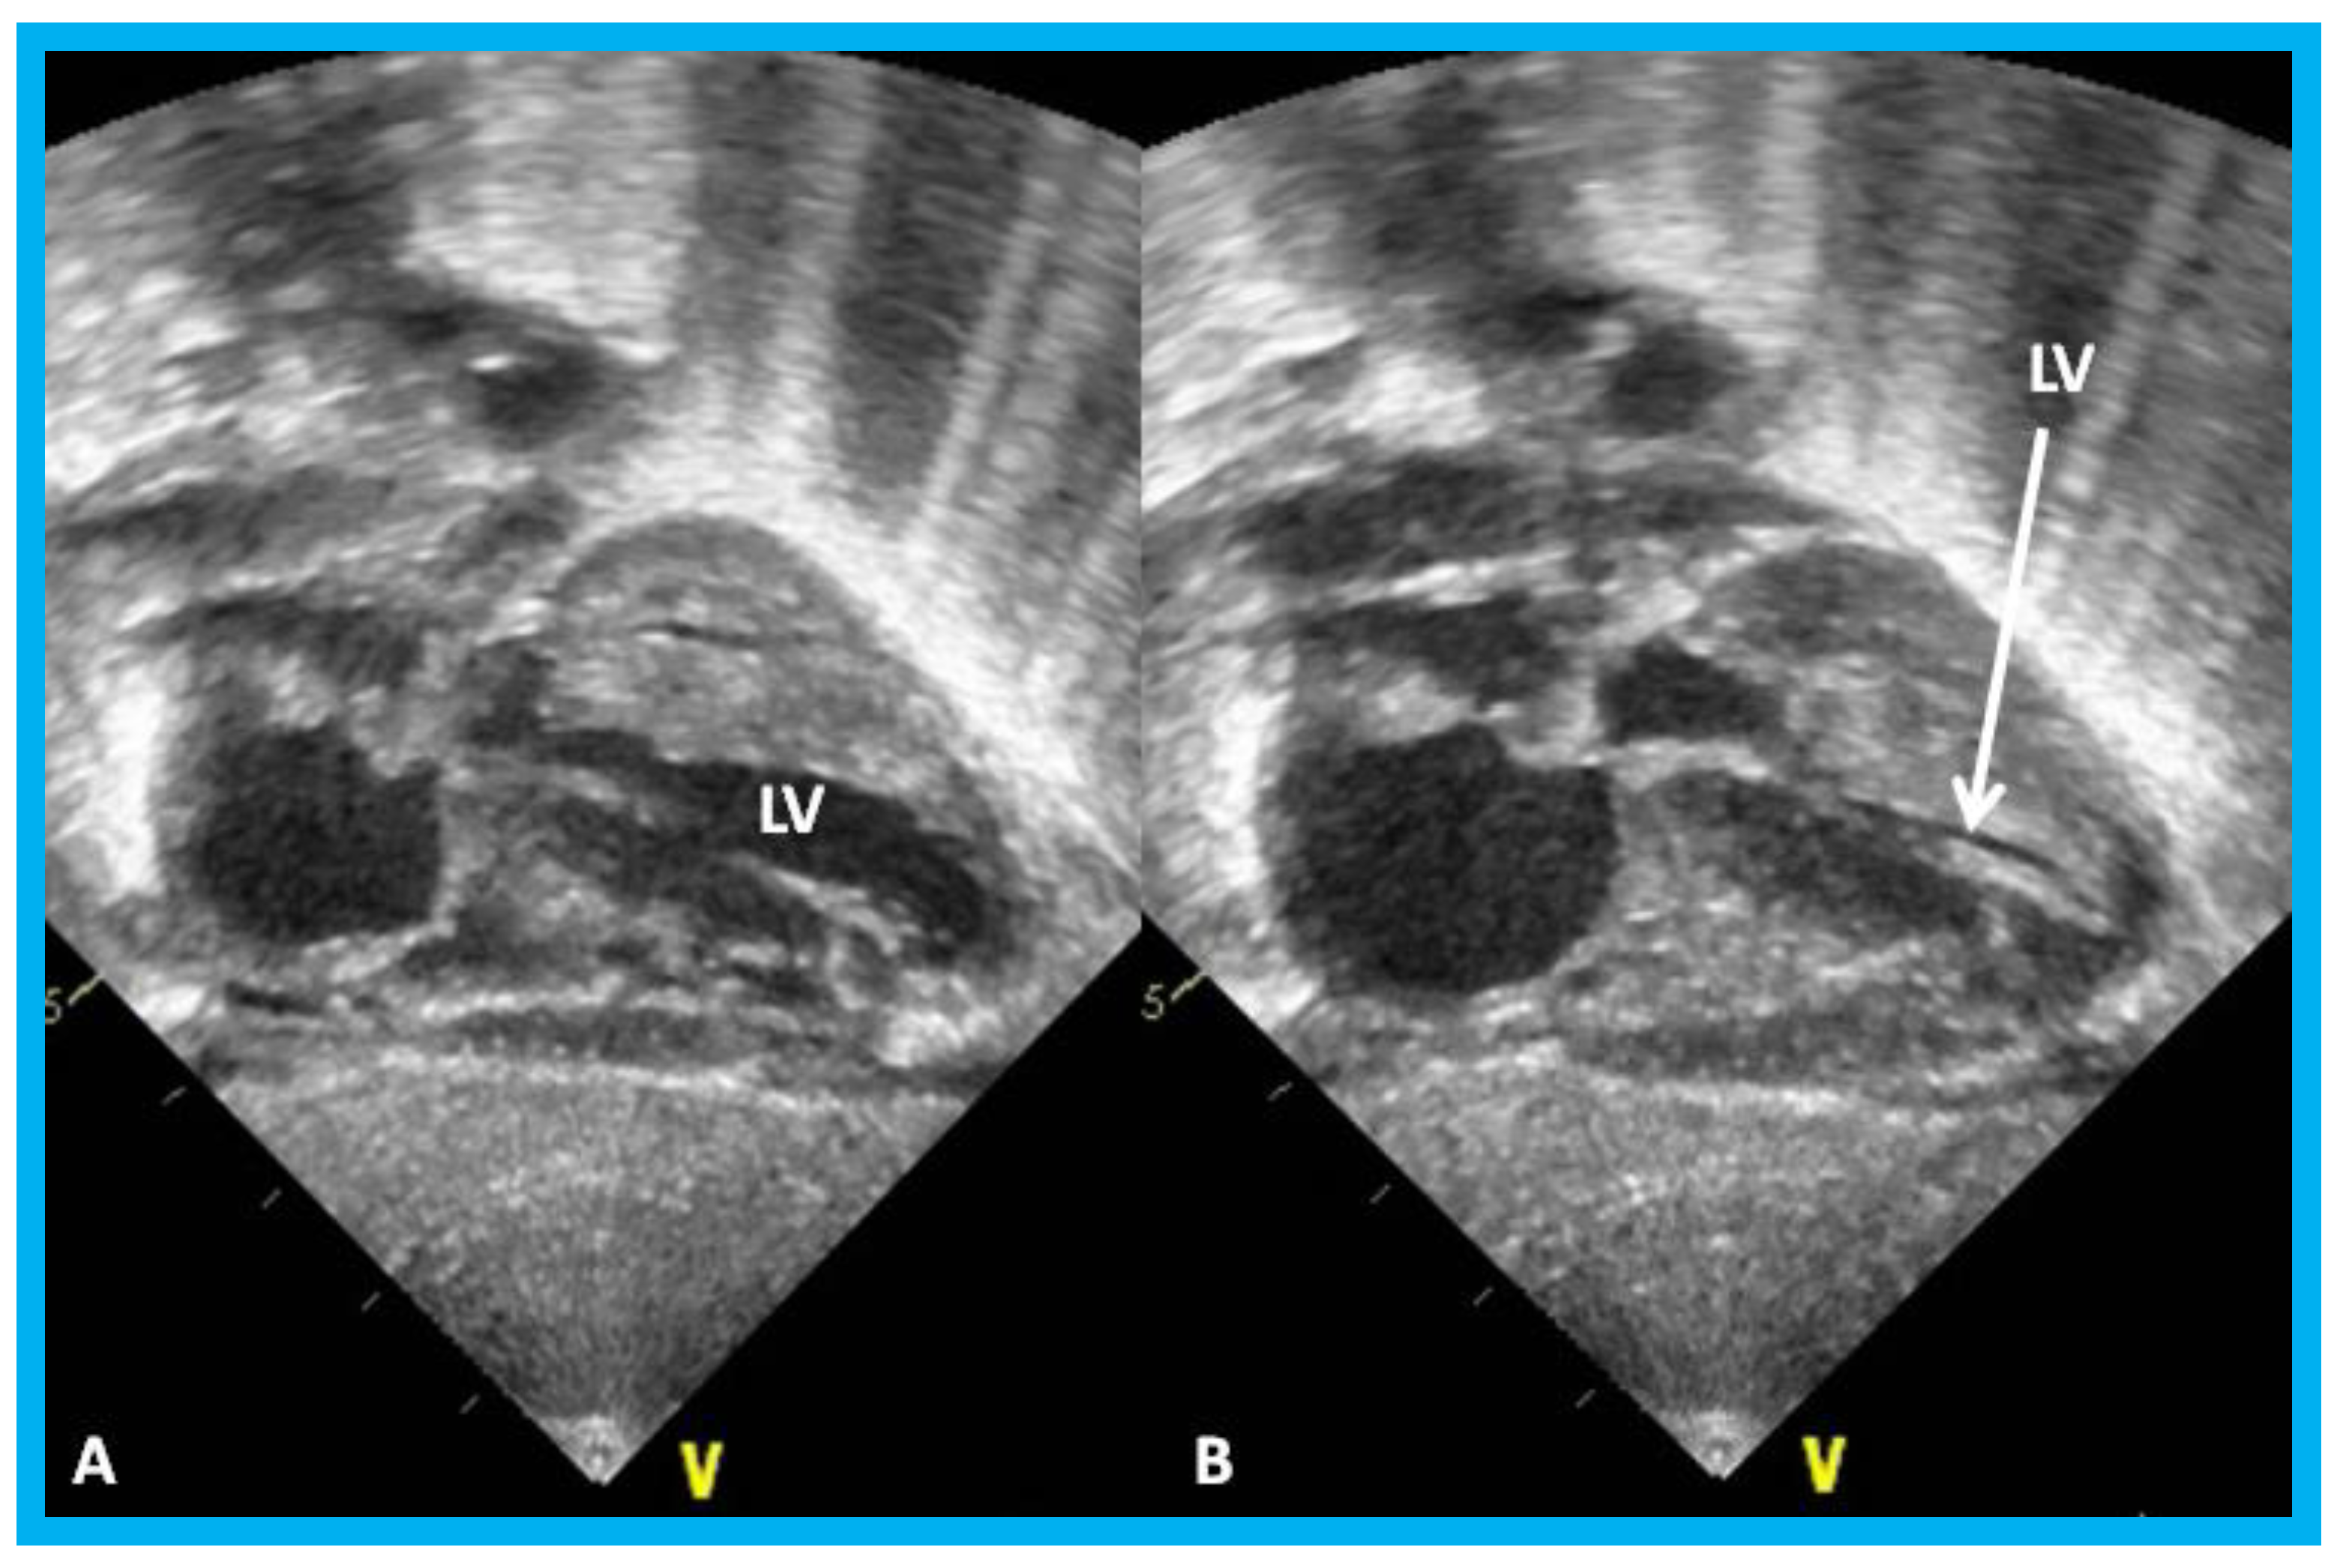

Figure 24. Apical four-chamber views of the left ventricle (LV) in end-diastole (LVED) in (A) and end-systole (LVES) in (B) demonstrating calculation of area shortening of the LV using Simpson’s rule: AS = (LVAd − LVAs)/LVAd (where AS is area shortening, LVAd is LV area in diastole, and LVAs is LV area in systole). The LV area shortening is 52% (see insert in (B)); normal values are 40 to 60%.